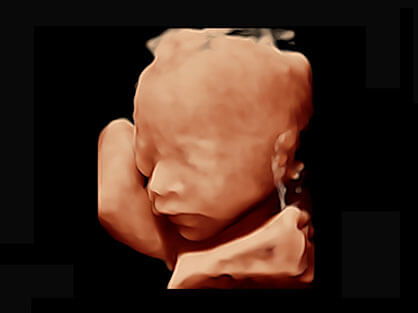

可同时显示组织结构表面和内部的轮廓信息,达到透视效果,为临床提供更丰富的诊断信息。

宽频带腹部凸阵探头和腹部容积探头、大角度腔内探头和腔内容积探头、独特的生殖专用曲柄探头,为妇产应用提供全面诊疗方案。

卵泡结构的自动识别和测量,可显示多组测量数据。

大角度腔内容积探头,可完整包络子宫及盆底结构,充分展示组织结构毗邻关系。